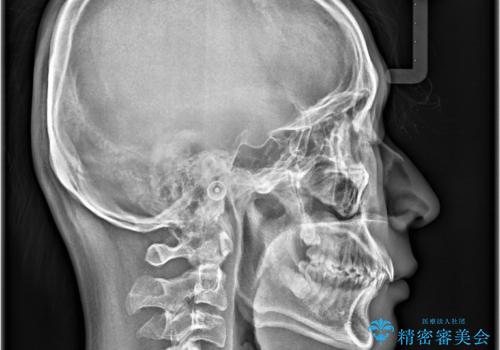

- 歯のデコボコと過蓋咬合を主訴に来院された患者様です。

アーチの拡大とIPRを行い非抜歯で治療を行いました。

歯を抜かずに叢生(デコボコ歯列)と過蓋咬合を改善する事が出来ました。